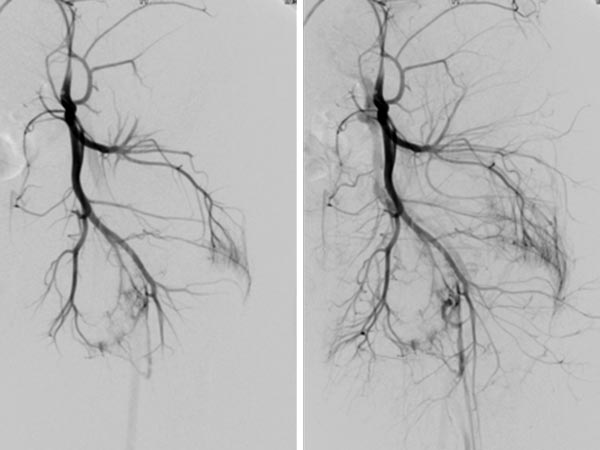

Digital subtraction angiography, with the catheter in the left superior gluteal artery, reveals multiple, barely identifiable small arteriovenous fistulas typical of the diffuse arteriovenous malformations seen in Parkes-Weber syndrome.

Superselective digital subtraction angiography via a microcatheter in the superior gluteal artery in a distal branch. The nidus of the fine fistulous arteriovenous malformation shows such fine shunts that they can hardly be resolved anatomically on angiography.